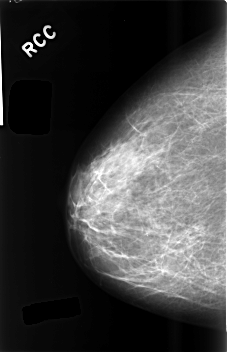

C_0489_1.RIGHT_CC

RIGHT_CC LINES 4576 PIXELS_PER_LINE 2944 BITS_PER_PIXEL 12 RESOLUTION 50 NON_OVERLAY

RIGHT_MLO LINES 4576 PIXELS_PER_LINE 2912 BITS_PER_PIXEL 12 RESOLUTION 50 NON_OVERLAY